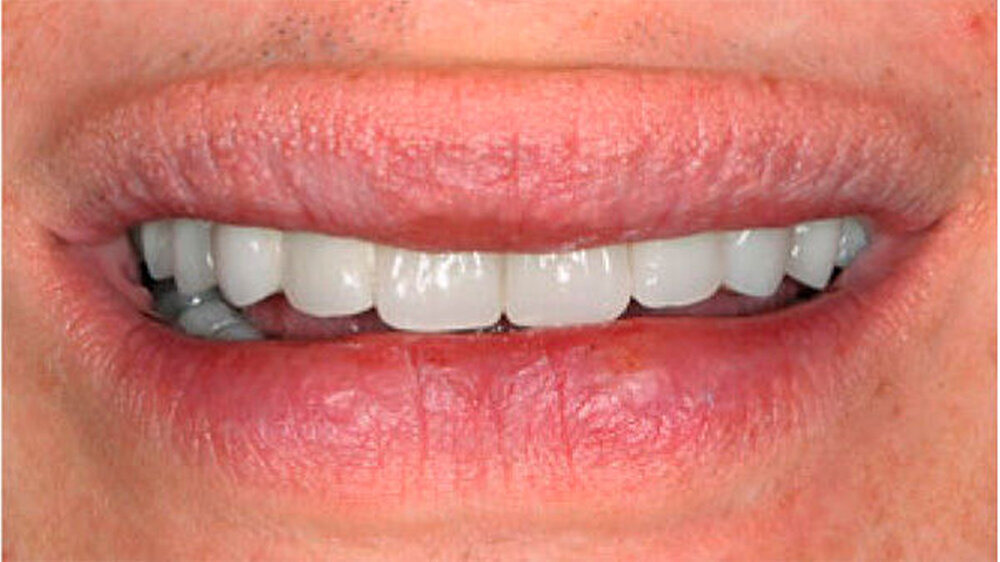

Die Patientin war mit einer knapp neunjährigen Teilprothese im Ober- und einer zweijährigen Totalprothese im Unterkiefer versorgt. Beim Lachen wurden die nicht mehr altersentsprechenden Prothesenzähne mit den deutlichen Randverfärbungen ersichtlich (Abb. 19). Das sagittale Wachstum des zahnlosen Unterkiefers führte in den letzten zwei Jahren aufgrund der verstärkten Kontakte im Frontzahnbereich zu einer beidseitigen Nonokklusion im Seitenzahnbereich (Abb. 20). Eine rasche Verbesserung der Ästhetik als auch der Funktion war unbedingt angezeigt, um das Selbstbewusstsein dieses puberalen Mädchens zu stärken.

Aufgrund des anatomisch sehr ungünstigen Prothesenlagers war der Erhalt der Restbezahnung im Oberkiefer anzustreben. Nach Kariesexkavation und Wurzelkanalbehandlung konnten beide Zähne mit einer Wurzelstiftkappe versorgt und die alten Prothesen entsprechend umgebaut werden. Im Anschluss an die Meisterabformungen und an die Ausrichtung der Wachswälle wurden die Modelle schädelbezogen einartikuliert, und die Prothesenzähne nach ästhetischen und funktionellen Richtlinien aufgestellt. Eine bilateral balancierte Okklusionsbeziehung konnte umgesetzt werden. Im Oberkiefer wurde eine gerüstverstärkte Totalprothese hergestellt, die auf den beiden Wurzelstiftkappen 16 und 26 verankert war. Im Unterkiefer konnte die Patientin mit einer Totalprothese versorgt werden (Abb. 21 bis 23).

Verbunden mit dem Umstand, dass die Patientin eine ausgeprägte Oligosialie aufweist, ist das Kariesrisiko und hiermit verbunden, auch das Pfeilerzahnrisiko deutlich erhöht. Regelmäßige Kontrolluntersuchungen sind zwingend. Da das Kieferwachstum noch nicht abgeschlossen ist, werden weitere zahnärztliche Behandlungen unumgänglich sein. Diese wenig invasive und relativ zeitnah umsetzbare Therapie erlaubte jedoch eine deutliche Verbesserung der Funktion und der Ästhetik und führte zu einer sichtlichen Stärkung des Selbstbewusstseins. Weitere zukünftige aufwendigere Behandlungsoptionen - insbesondere implantatgetragene Restaurationen - können nun nach abgeschlossenem Wachstum, auf der Basis einer ästhetisch und funktionell akzeptablen Ausgangslage, im Behandlungsteam geplant werden.